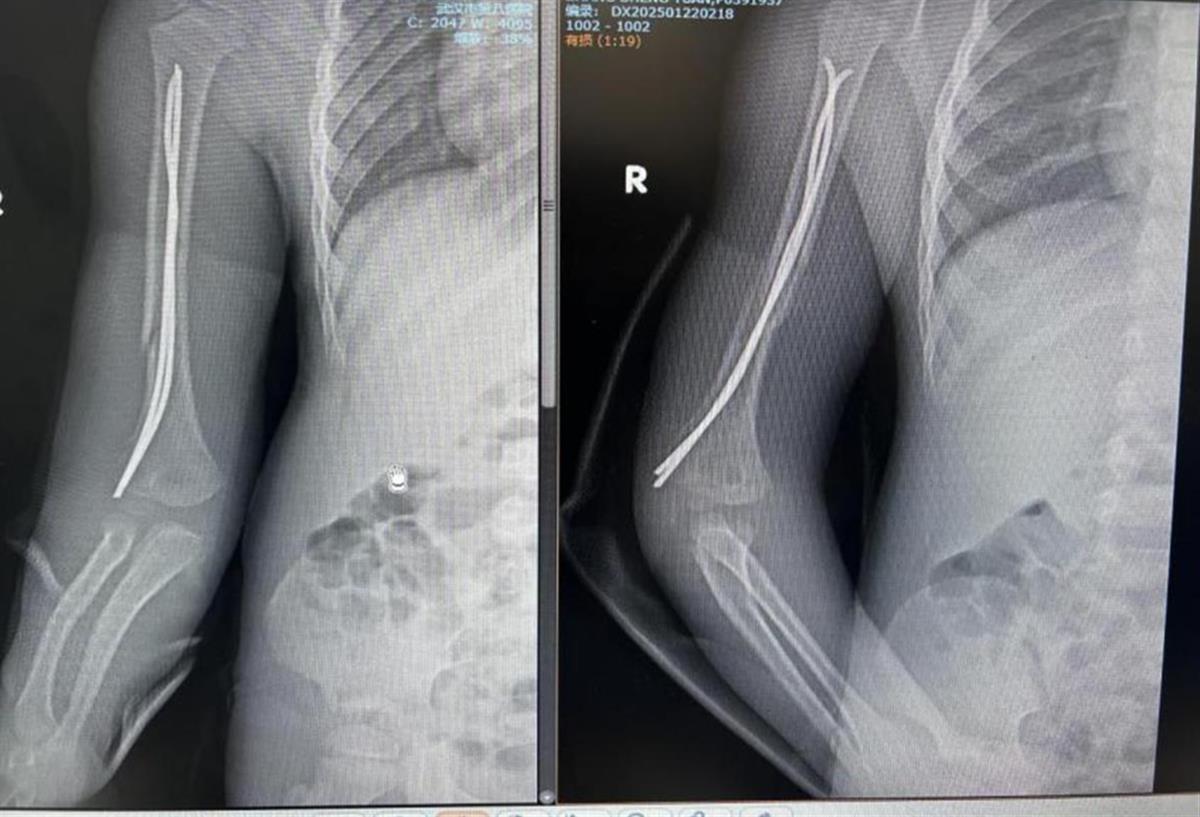

经过术前评估,创伤外科团队为乐乐制定了手术方案,并在麻醉科、手术室的配合下,将两根髓内针预弯成C型和S型,精准定位后固定骨折端。手术不到1小时,乐乐出血量极少。术后X光片显示,骨折端对位良好。

术后复查X片恢复良好